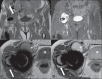

Soft tissue complications following hip arthroplasty may occur either in cases of total hip arthroplasty or in hip resurfacing, a technique that has become popular in cases involving young patients. Both orthopedic and radiological literatures are now calling attention to these symptomatic periprosthetic soft tissue masses called inflammatory pseudotumors or aseptic lymphocytic vasculites-associated lesions. Pseudotumors are associated with pain, instability, neuropathy, and premature loosening of prosthetic components, frequently requiring early and difficult reoperation. Magnetic resonance imaging plays a relevant role in the evaluation of soft tissue changes in the painful hip after arthroplasty, ranging from early periprosthetic fluid collections to necrosis and more extensive tissue damage.